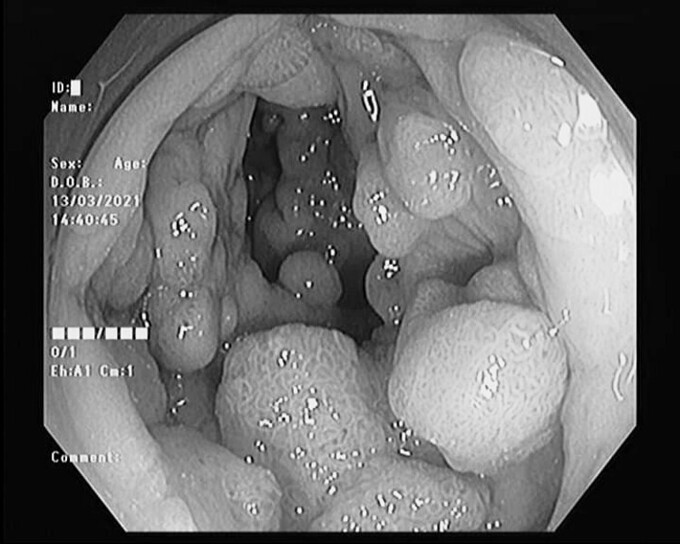

Các bác sĩ Bệnh viện Đa khoa Hùng Vương, ngày 15/3 nội soi đại tràng của hai người, nhận thấy hàng trăm polyp với nhiều kích cỡ từ 3 mm đến 2 cm, dày đặc từ manh tràng đến hết trực tràng. Các bác sĩ Chuyên khoa Ung bướu hội chẩn cùng chuyên gia Bệnh viện K, kết luận hai bệnh nhân mắc Hội chứng đa polyp gia đình.

Bác sĩ Trần A Pao, Phó trưởng Khoa Ung bướu, nhận định nếu không xử trí sớm, chắc chắn bệnh sẽ tiến triển thành ung thư đại trực tràng. Hai bệnh nhân cần thực hiện phẫu thuật cắt đại tràng càng sớm càng tốt.